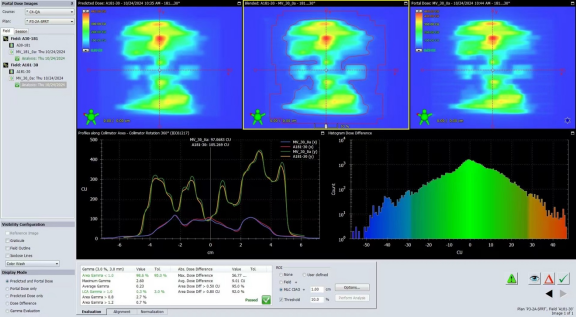

在治疗过程中,使用TrueBeam平台的精密计划系统,确保了每一剂量都能够精准作用于肿瘤病灶,同时最大限度地减少了对正常肝脏组织的损伤。从治疗计划到实施,整个流程保持高水平的精度和稳定性。